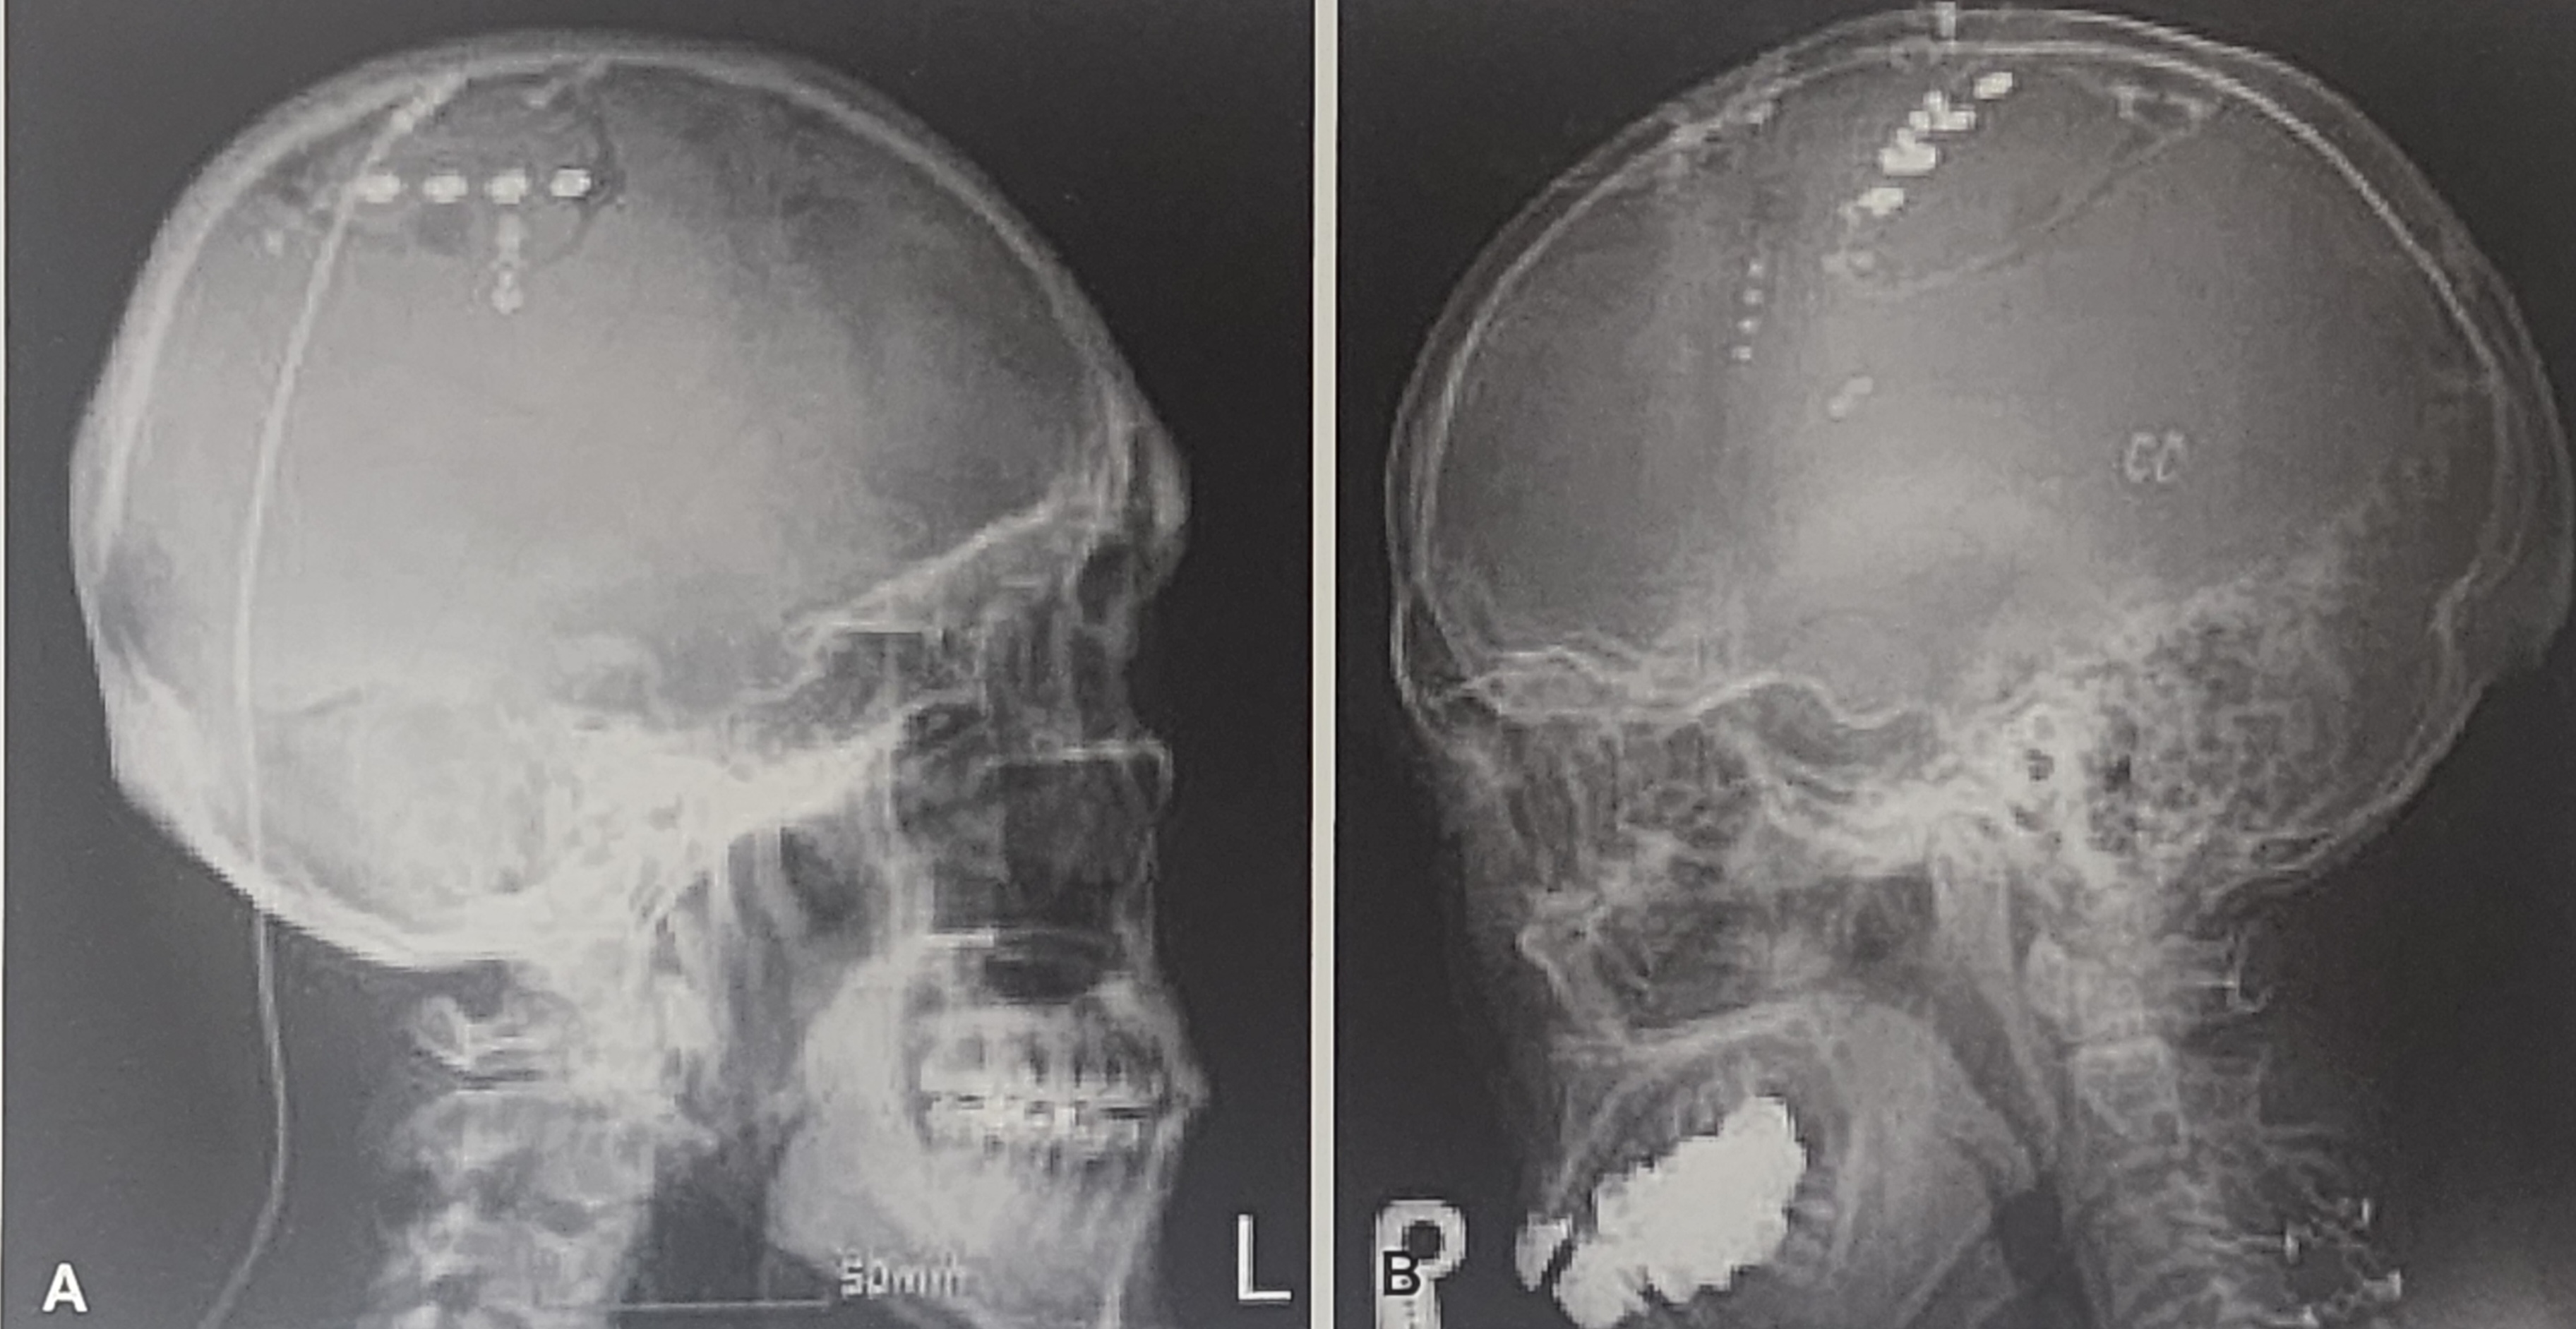

전극을 삽입하는 방법에는 크게 경막외법(epidural implantation) 과 경막하법(subdural implantation) 이 있다. 대부분의 연구에서 경막외법이 더 안전하며 효과적이라고 보고되었다.

전극의 위치는 중심전회(precentral gyrus) 에 정확하게 배치해야 하며, 이를 위해 MRI, CT, 전기생리학적 검사(MEP, SEP) 등을 활용하여 중심전회의 체성감각 영역을 찾아내는 과정이 필요하다.

- Saitoh 등은 중심구에 직각 방향(transverse) 으로 전극을 삽입하는 것이 더 좋은 결과를 나타낼 수 있다고 보고했다.

- 운동피질자극술에서 중요한 전극(active electrode)의 위치는 환상전극(halo electrode) 을 정확하게 포함하는 방식이 효과적이다.